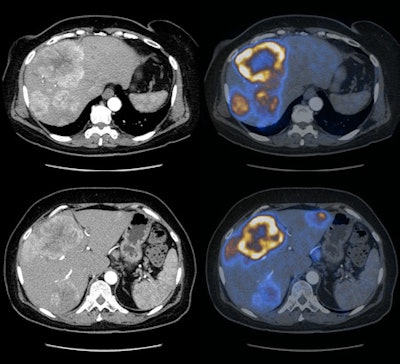

| Contrast-enhanced CT (left) of a solid papillary neuroendocrine carcinoma with corresponding liver metastases, compared to the same region with DOPA-enhanced PET/CT (right). Images courtesy of Dr. Patrick Veit-Haibach. |

With the additional information provide by DOPA-PET/CT, which included resection of primary tumors, metastases, and newly found lesions, therapy changed in 17 (26%) of the 65 cases from surgery to chemotherapy. In three cases, planned therapy was spared.

Based on the results, the researchers concluded that DOPA-PET/CT "with contrast enhancement is significantly superior to DOPA-PET alone and contrast-enhanced CT, at least for the lesion-based analysis," Veit-Haibach concluded. "We found the potential for detecting very small primary lesions, and we found in our patient population a very significant therapeutic influence" to better manage patients with neuroendocrine tumors.